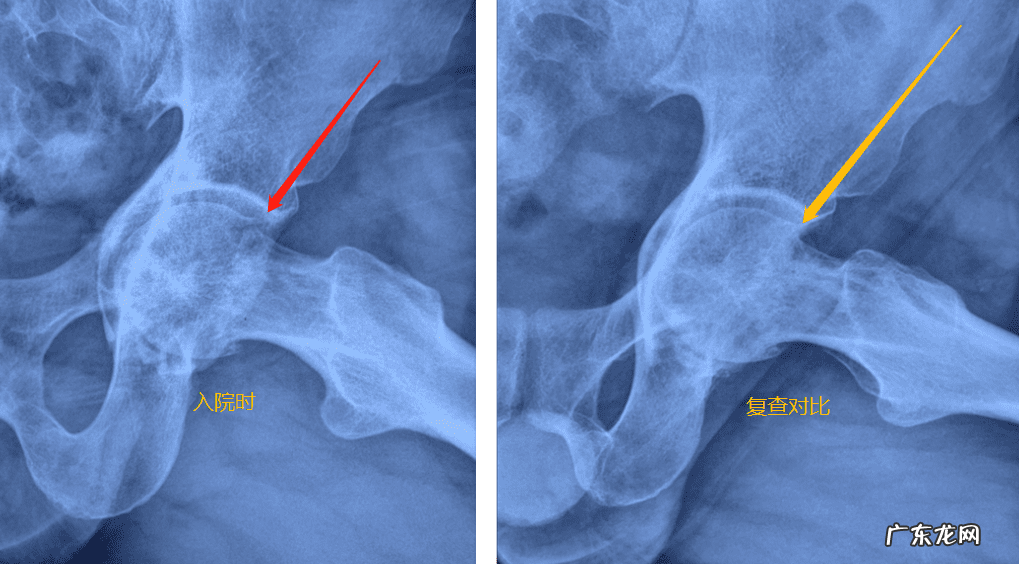

股骨头坏死的后遗症包括股骨头严重的变形、塌陷,关节间隙的变窄,骨关节炎,关节融合等,主要是股骨头形态的问题,后遗症目前保守,无法很好地解决,但是后遗症时候可以早期避免和预防出现,所以股骨头坏死能不能治好,不能以后遗症不能解决来判断疾病不能治疗,西医看待问题,就是拿后遗症不能解决来给股骨头判的“死刑”另外股骨头坏死的干预治疗,在很大程度上是为了避免后遗症的产生或者减少后遗症的产生,从而缩短疾病的恢复时间,解决病痛,以及避免因疾病所致的严重功能障碍和生活困难问题 。